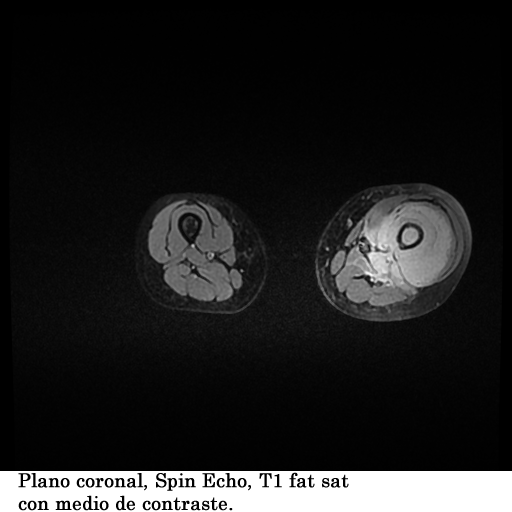

Se coloco al paciente en decúbito supino, utilizando una bobina fase array, haciendo adquisiciones en los planos axial, sagital y coronal, secuencias, spin echo, eco de gradiente e hibridas, potenciadas a T1, T2 y DP, secuencias Steer, y se obtuvieron imágenes con saturación de grasa.

1. Edema de tejidos blandos que infiltra los músculos del muslo en su tercio medio y distal

2. Fractura patológica de tercio proximal de la diáfisis femoral izquierda

3. Engrosamiento del periostio del tercio medio y distal de la diáfisis femoral izquierda